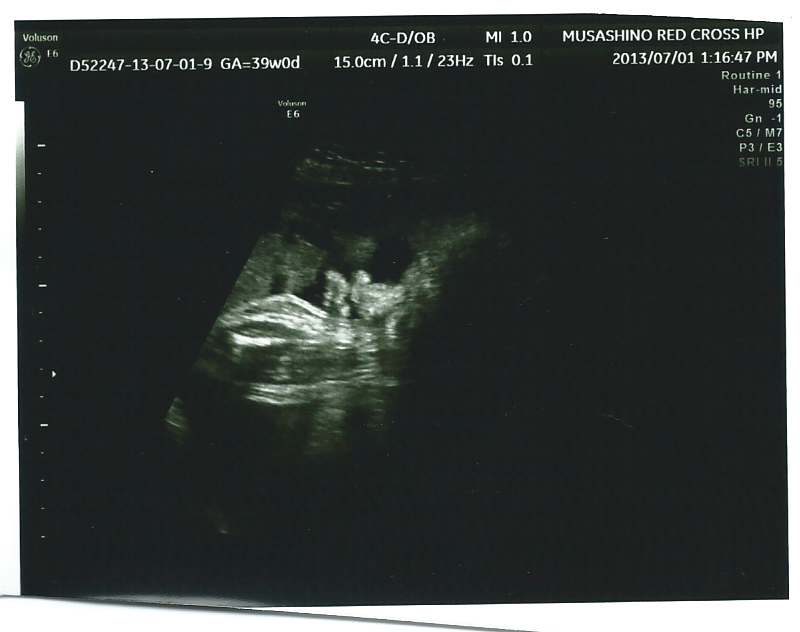

echo